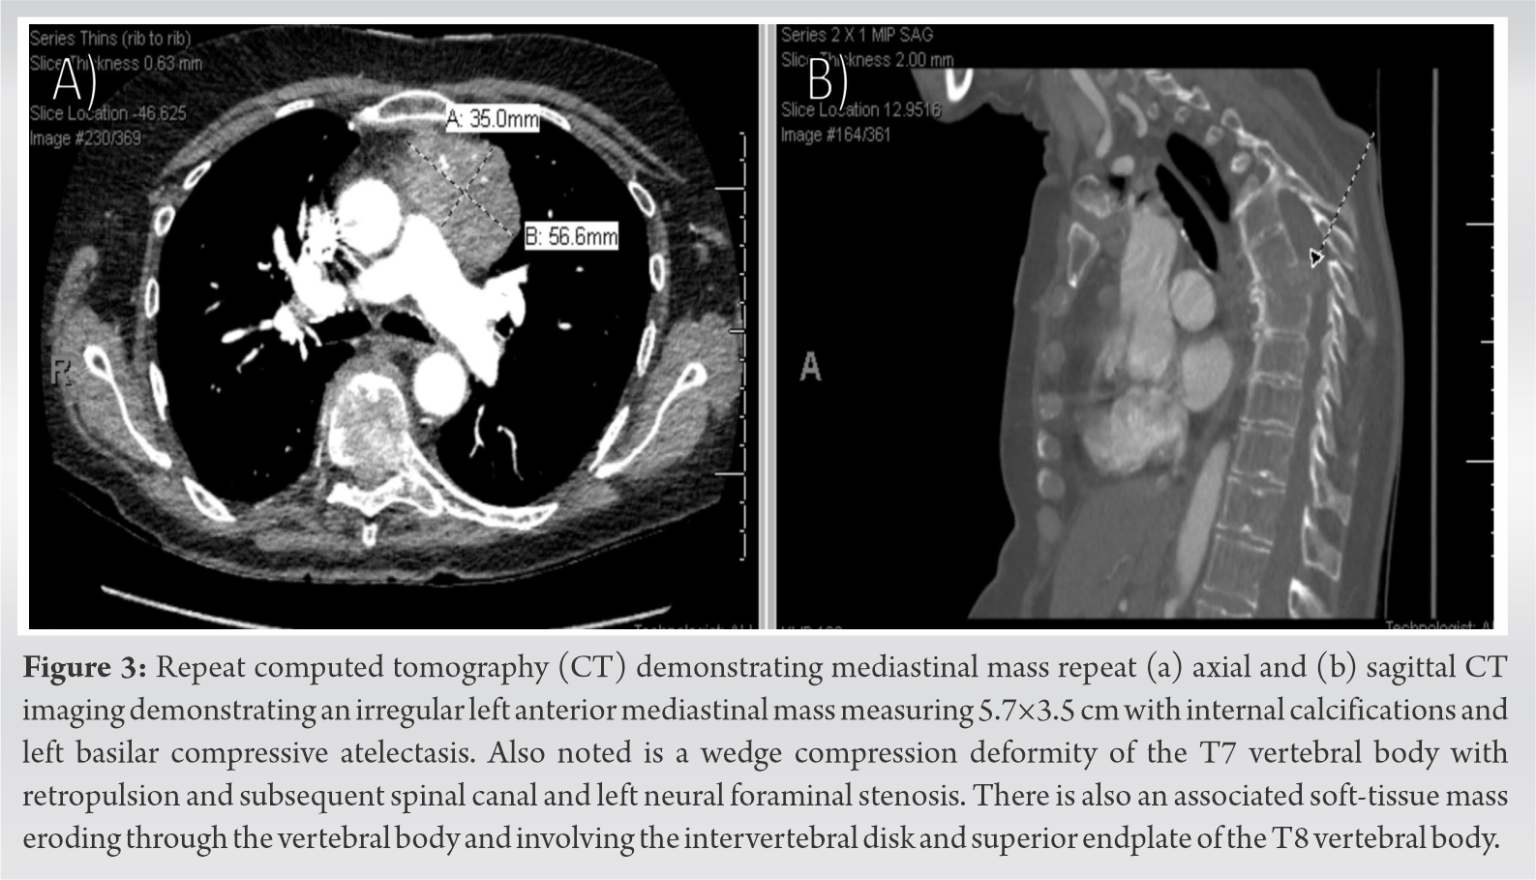

From jocr.co.in

Type A Thymoma with Spinal and Cranial Metastases A Case Report Can Thymoma Grow Back When diagnosing thymomas, doctors use a thymoma staging system to help guide. You’ll still need to visit. The two main forms of tets are: thymoma is one of two types of thymic epithelial tumors, the other being thymic carcinoma. recurrent thymoma and thymic carcinoma are cancers that have recurred (come back) after treatment. however, often, both types. Can Thymoma Grow Back.